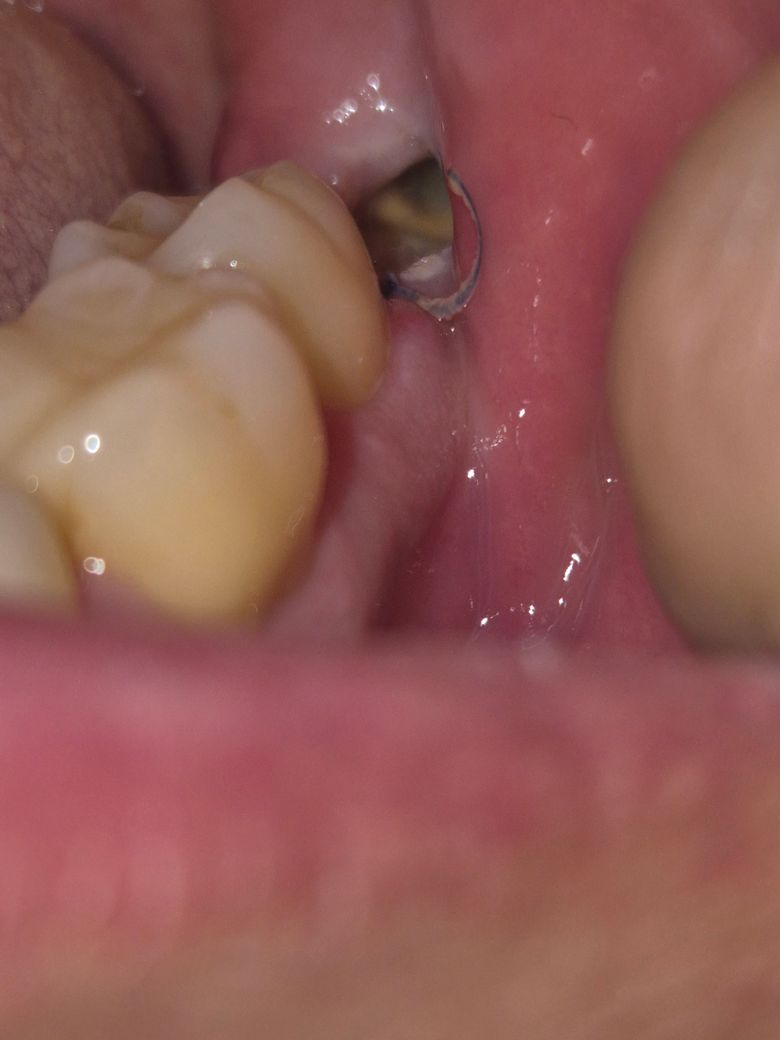

매복사랑니 발치후 사진좀 봐주세요!

매복사랑니를 5일전에 뽑았는데, 통증이 오늘부터 좀 심한거같습니다.

혹시 드라이소켓이나 다른 부작용일까요

욱씬욱씬 통증이 있고 입을 벌릴때도 아프네요..

• 1번 째 사진

• 매복 사랑니 발치 이후 드라이소켓은 2~3일 내에 나타나게 됩니다. 일주일이 다되어가는 상황에서 나타나는 통증은 음식물 저류이거나 해당 부위의 자극으로 인하여 나타날 가능성이 큽니다. 또한 드라이소켓은 여기에 글을 쓰지 못할 정도로 통증이 심합니다.

• 현재 드라이소켓이 생긴 것은 아니며, 해당부위가 이상없이아물고 있는 것으로 보입니다. 만약 통증으로 인해 불편감이 있는 경우에는 소염진통제 복용을 권하며,1-3주간은 불편감이 나타날수 있습니다.

• 사진으로 봤을 경우에는 혈병이 제대로 생성되지 않아 치유가 늦어지고 있는 것으로 보입니다 발치한 부위를 자극하지 않는 것이 좋으며 대부분 발치한 부위는 2주가 지나면 아물게 됩니다

• 사진만으로는 판별이 어렵지만 가능성은 있는것으로 보입니다. 통증이 계속 심해지는 것이라면 치과에 내원하셔서 검사를 받아보시는 것이 좋겠습니다